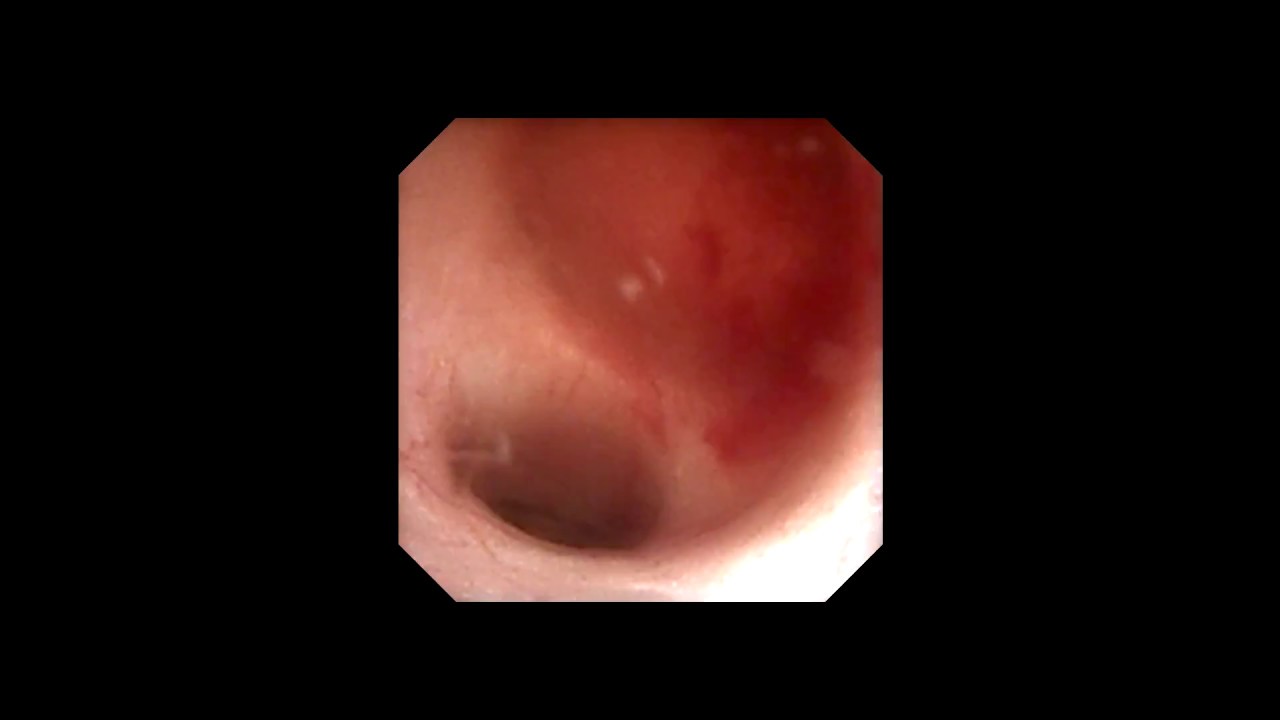

Biopsia prostática transrectal

Es un estudio que se realiza con la intención de diagnosticar cancer en la próstata, y se indica cuando hay alteraciónes en la exploración rectal realizada por su medico o una elevación del antígeno prostático especifico en la sangre.

La biopsia se realiza con un equipo de ultrasonido donde se visualiza la próstata a través del recto y se toman varios fragmentos de ambos lóbulos prostáticos (12-16) para su análisis. Se realiza con anestesia local o sedación, previa valoración por su medico. Requiere de una preparación con medicamentos y enemas previos a la biopsia para evitar complicaciones. El resultado de la biopsia puede ser positivo a cancer o puede mostrar resultados benignos.